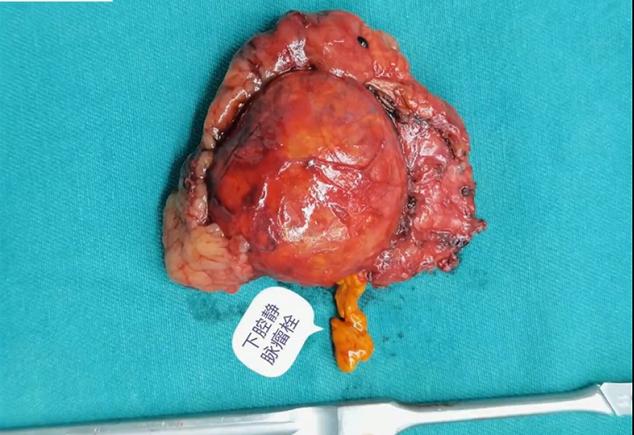

肾上腺肿瘤的下腔静脉瘤栓较为少见,本手术过程中意外发现中央静脉及下腔静脉瘤栓,术中隐约可见瘤栓在下腔静脉里漂荡,可能因瘤栓较细,术前CT难以发现。 由于右侧中央静脉太短,经反复尝试无法通过直接钳夹完整取栓后,术者最终选择切开血管取栓。后腹腔空间小且手术部位位置深,下腔静脉取栓手术难度较高。原则上应阻断瘤栓的近端及远端,但考虑到经后腹腔阻断瘤栓近心端下腔静脉操作困难,难以进行,故选择结扎切断两根肝短静脉、阻断瘤栓远端下腔静脉,然后调高气腹压以对抗减低了的腔静脉压,以达到少出血甚至不出血的目的。 手术演示